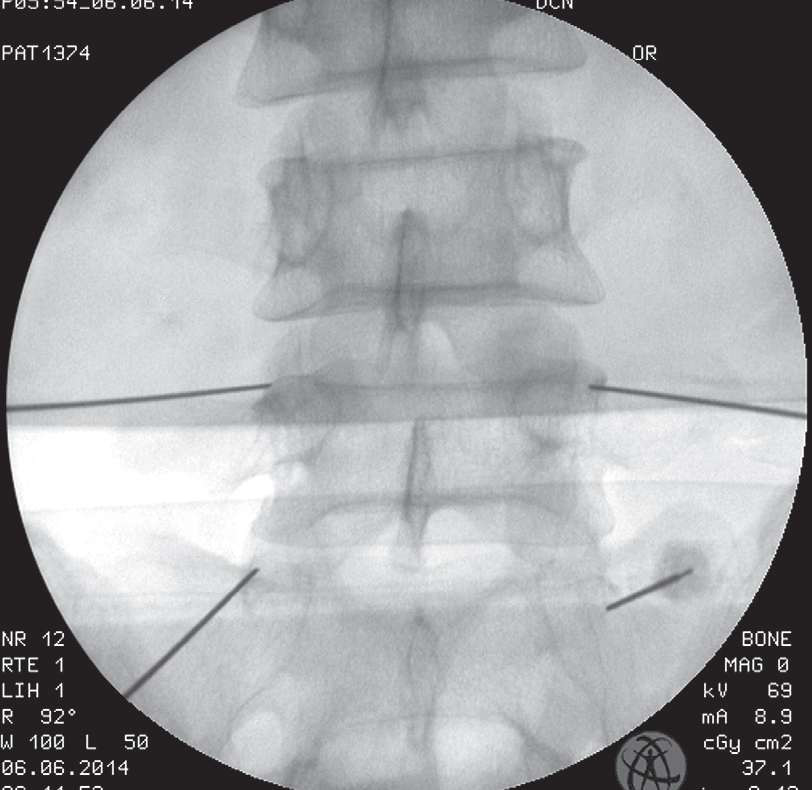

3.具体操作 在透视下标记出靶椎间孔的部位。进针点旁开棘突5~6cm,斜行向前向内,触及上关节突外侧部分后,改变方向再向深部刺入,感到阻力消失感后,即已进入椎间孔内(图4-49)。但不应过深进针,以免损伤神经根周围的血管组织或误入蛛网膜下腔。抽吸无回血及脑脊液后注入药液2~3ml,能产生整个神经根周围的阻滞作用。椎间孔穿刺注药法可以在C形臂机下应用(图4-50、图4-51),也可不在透视下应用。但其穿刺技术要求较高,必需经验丰富的医师操作。

图4-49 穿椎间孔注射和选择性神经根注射穿刺针最终位置的侧面观

图4-50 放射透视时患者的体位,患者体位和C形臂机的角度

图4-51 在放射透视监护下进针